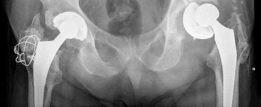

Postoperative Radiographs

(Figs. 19.25 and 19.26)

Reconstruction techniques : A hemispherical socket was placed; however, in the presence of posterior wall deficiency, a buttress augment was utilized to support the socket. The cup was fixed with multiple screws, and demineralized bone matrix was placed behind the acetabulum. The augment and the acetabular components were adjoined with the use of cement (Figs. 19.25 and 19.26).